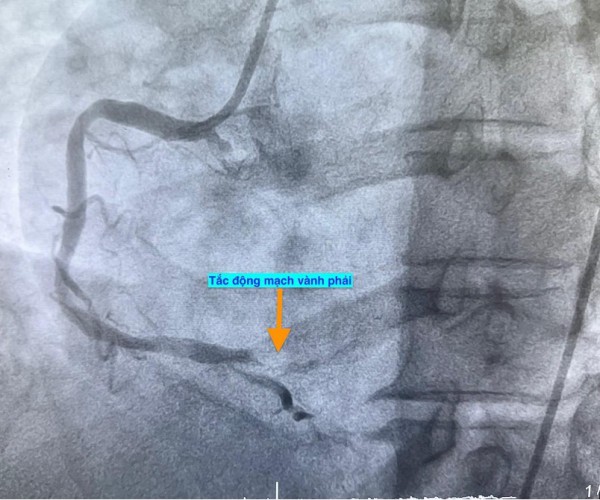

Trường hợp thứ hai, lúc 9 giờ 5 phút, nam bệnh nhân 53 tuổi nhập viện vì chóng mặt và nóng rát thượng vị. Điện tâm đồ ghi nhận nhồi máu cơ tim cấp vùng dưới. Kết quả chụp mạch vành xác định bệnh nhân cũng bị tắc động mạch vành phải.

Hình ảnh chụp mạch vành cho thấy các bệnh nhân bị tắc mạch máu tim (do mảng xơ vữa, huyết khối) dẫn đến tình trạng thiếu máu cục bộ và nhồi máu cơ tim cấp

ẢNH: BV